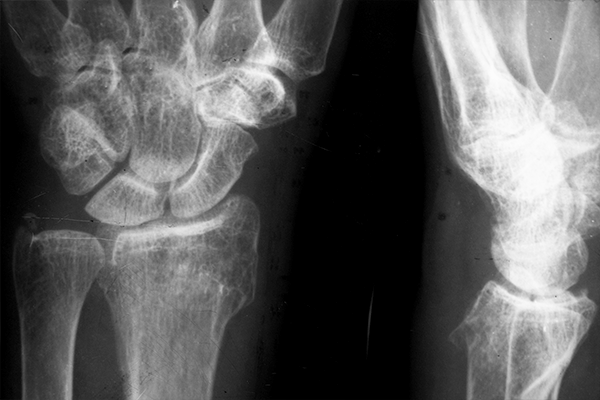

Magnesium (Mg)-based implants are highly attractive for the orthopedic field and may replace titanium (Ti) as support for fracture healing. To determine the implant–bone interaction in different bony regions, we implanted Mg-based alloy ZX00 (Mg < 0.5 Zn < 0.5 Ca, in wt%) and Ti-screws into the distal epiphysis and distal metaphysis of sheep tibiae. The implant degradation and osseointegration were assessed in vivo and ex vivo after 4, 6 and 12 weeks, using a combination of clinical computed tomography, medium-resolution micro computed tomography (µCT) and high-resolution synchrotron radiation µCT (SRµCT). Implant volume loss, gas formation and bone growth were evaluated for both implantation sites and each bone region independently. Additionally, histological analysis of bone growth was performed on embedded hard-tissue samples. We demonstrate that in all cases, the degradation rate of ZX00-implants ranges between 0.23 and 0.75 mm/year. The highest degradation rates were found in the epiphysis. Bone-to-implant contact varied between the time points and bone types for both materials. Mostly, bone-volume-to-total-volume was higher around Ti-implants. However, we found an increased cortical thickness around the ZX00-screws when compared with the Ti-screws. Our results showed the suitability of ZX00-screws for implantation into the distal meta- and epiphysis.

Magnesium (Mg) alloys have become a potential material for orthopedic implants due to their unnecessary implant removal, biocompatibility, and mechanical integrity until fracture healing. This study examined the in vitro and in vivo degradation of an Mg fixation screw composed of Mg-0.45Zn-0.45Ca (ZX00, in wt.%). With ZX00 human-sized implants, in vitro immersion tests up to 28 days under physiological conditions, along with electrochemical measurements were performed for the first time. In addition, ZX00 screws were implanted in the diaphysis of sheep for 6, 12, and 24 weeks to assess the degradation and biocompatibility of the screws in vivo. Using scanning electron microscopy (SEM) coupled with energy dispersive X-ray spectroscopy (EDX), microcomputed tomography (μCT), X-ray photoelectron spectroscopy (XPS), and histology, the surface and crosssectional morphologies of the corrosion layers formed, as well as the bone-corrosion-layer-implant interfaces, were analyzed. Our findings from in vivo testing demonstrated that ZX00 alloy promotes bone healing and the formation of new bone in direct contact with the corrosion products. In addition, the same elemental composition of corrosion products was observed for in vitro and in vivo experiments; however, their elemental distribution and thicknesses differ depending on the implant location. Our findings suggest that the corrosion resistance was microstructure-dependent. The head zone was the least corrosion-resistant, indicating that the production procedure could impact the corrosion performance of the implant. In spite of this, the formation of new bone and no adverse effects on the surrounding tissues demonstrated that the ZX00 is a suitable Mg-based alloy for temporary bone implants.

A lean magnesium-zinc-calcium alloy ZX00 used for bone fracture stabilization in a large growing-animal model